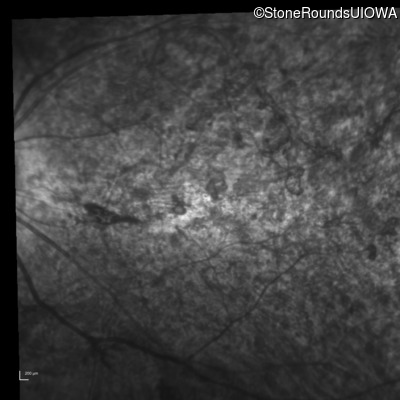

Infrared Fundus Photograph - Right - 20/400 sc

Exemplar